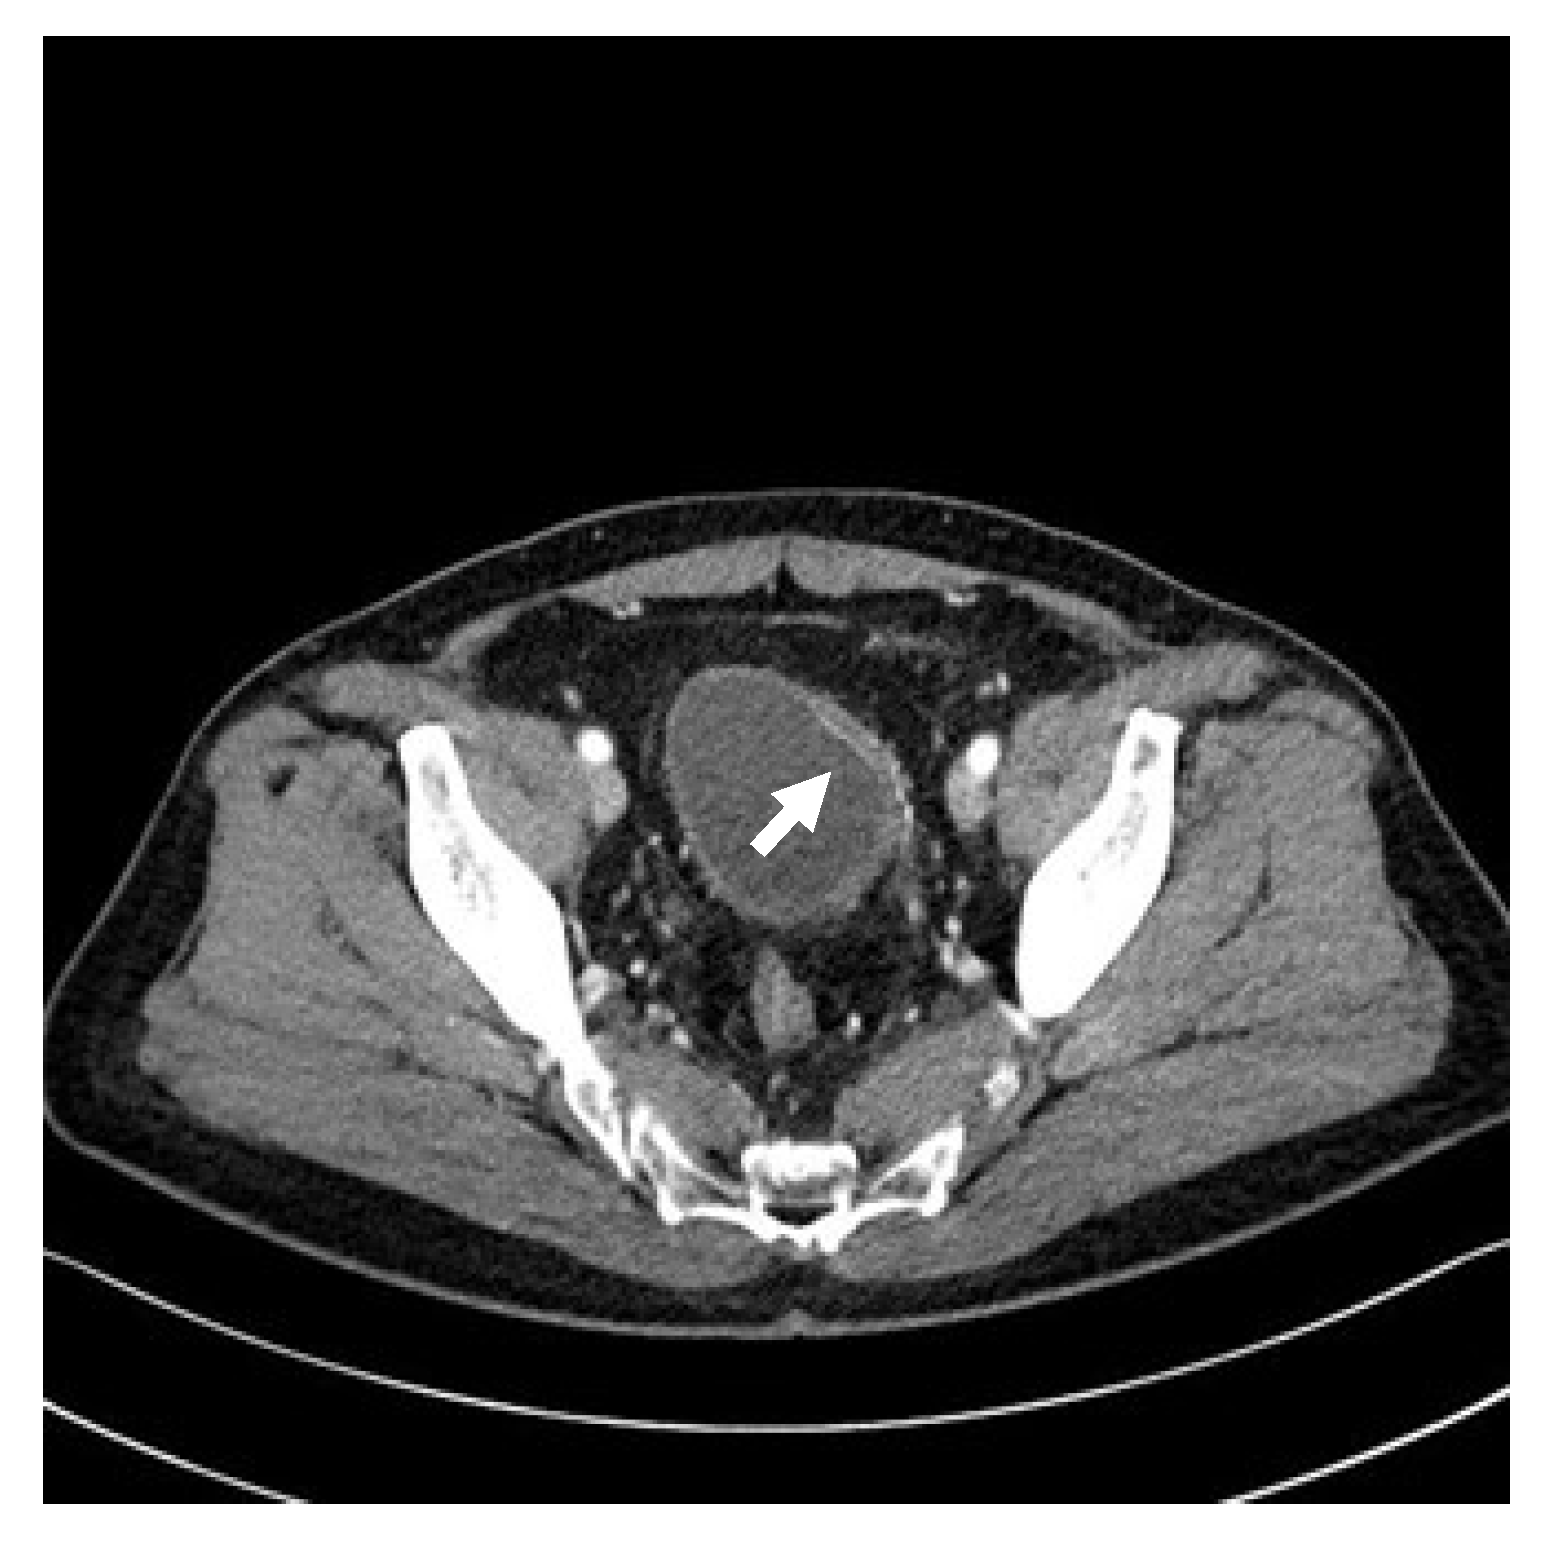

2. Detailed Case Description